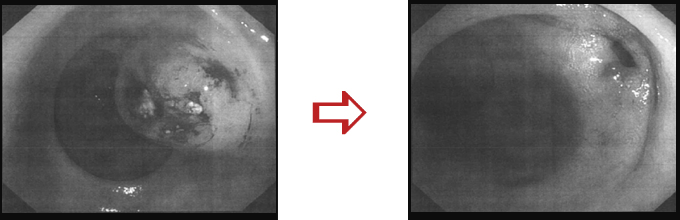

胃癌、リンパ転移

横内漢方治療前と後